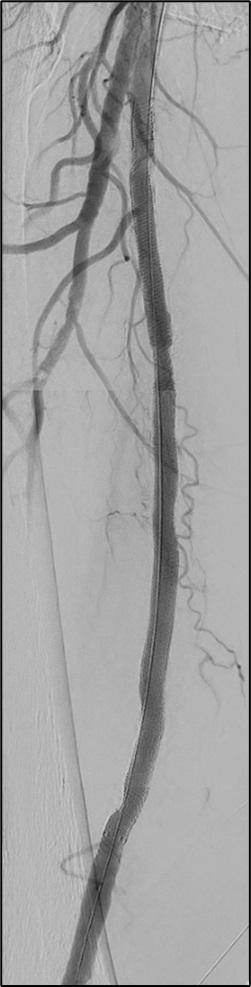

Pilot testing has shown that a new framework—dubbed Endo-STAR—can be used to describe and standardise endovascular interventions for peripheral arterial disease (PAD) within a randomised controlled trial (RCT) protocol and monitor adherence to the protocol over the course of a trial. Ewa M Zywicka (University of Bristol Medical School, Bristol, UK) shared this conclusion during the Prize Session at the recent European Society for Vascular Surgery (ESVS) annual meeting (24–27 September, Kraków, Poland).

ZYWICKA BEGAN BY NOTING THAT

rigorous evaluation of novel lower-limb endovascular interventions is “critically important” to ensure adoption of effective technologies and rejection of those that are ineffective or harmful.

The presenter continued that poor reporting of RCTs limits the evaluation of technologies for lower-limb endovascular interventions, highlighting a recent study in which more than half of RCTs did not adequately describe interventions, and almost 80% did not report any form of standardisation.

The aim of Zywicka and colleagues’ present study, therefore, was to develop a specific framework for describing and standardising endovascular lower-limb interventions within clinical trials.

Zywicka explained to the ESVS audience that the Endo-STAR framework was developed using qualitative research methodology and the Enhancing the Quality and Transparency of Health Research (EQUATOR) methodological framework. The presenter added that trial reports and associated protocols identified in a recent systematic review of endovascular infrainguinal lower-limb RCTs for PAD provided the data for developing the preliminary framework.

Going into more detail about the research methods used, Zywicka detailed that a framework approach to thematic analysis of qualitative data was employed to code and categorise text into steps and components of endovascular infrainguinal interventions.

Subsequently, focus groups were conducted

with key international stakeholders such as clinical practitioners—namely vascular surgeons, interventional radiologists, angiologists and cardiologists—trialists, industry representatives and journal editors to refine the framework and consider clarity and feasibility issues. Zywicka noted that the framework was updated based on this feedback, and

a consensus between stakeholders was reached via a modified Delphi-style questionnaire.

Finally, Zywicka shared, the framework was refined through cognitive interviews with trialists to test the real-world feasibility of using the Endo-STAR framework in contemporary endovascular RCTs. An online version of the Endo-STAR framework

Twenty-four key stakeholders participated in three focus groups, contributing to the refinement of the framework

was developed to facilitate implementation and dissemination.

At ESVS, Zywicka informed attendees that the preliminary framework was developed after including data from 112 RCTs evaluating endovascular infrainguinal interventions for PAD.

Zywicka relayed that 24 key stakeholders participated in three focus groups, contributing to the refinement of the framework, and all 24 participants took part in the consensus questionnaire. After the first round of the questionnaire, the presenter continued, an agreement above 85% was reached for each framework section. Ten trialists involved in contemporary endovascular trials took part in pilottesting the framework.

Ultimately, Zywicka reported, the Endo-STAR framework was structured into six main sections: 1) expertise of the professional delivering the intervention, 2) setting/location of the intervention, 3) anaesthesia provided for the intervention, 4) imaging used at the time of the intervention, 5) intervention components: access, crossing the lesion, treating the lesion (including specific steps and details related to all currently available endovascular devices) and closure of the artery, and 6) pharmacological interventions.

In discussion time following Zywicka’s talk, jury member Jon Boyle (Cambridge University Hospitals NHS Foundation Trust, Cambridge, UK) asked how the framework might help in terms of monitoring long-term outcomes of endovascular interventions, to which the presenter responded: “What we are aiming to achieve with this framework is to know what has been done in a trial […] we expect that actually being able to know and clearly describe what was done in a trial can be used to easily compare trials and even potentially compare results in the long term as well.”